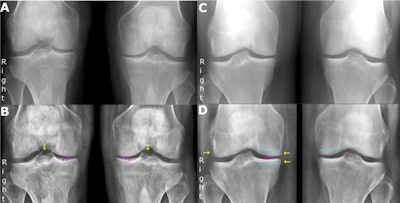

The researchers retrospectively enrolled 50 consecutive patients with weight-bearing, nonfixed-flexion posteroanterior radiographs of both knees (100 knees) acquired at their hospital between September 2019 and October 2019. A research radiographer reviewed all images to ensure a full range of osteoarthritis severity was covered under the Kellgren and Lawrence system, which offers five grades, from normal to severe.

Six radiology professionals were included as readers: two musculoskeletal specialists with more than 10 years of clinical experience each, two reporting technologists with more than 10 years of musculoskeletal reporting experience but no prior experience with the Kellgren and Lawrence system, and two resident radiologists. The AI tool acted as the seventh reader.

Analysis revealed agreements between the AI tool and the consensus between the two musculoskeletal specialists was 0.88, while agreement between the specialists themselves was 0.89, according to the findings.

Intrarater agreements for the specialists were 0.96 and 0.94, and 1 for the AI tool. For the AI tool, ordinal weighted accuracy was 97.8%.

The AI tool's agreement with the two reporting technologists was 0.85% and 0.82%, and agreement with the radiology residents was 0.85% and 0.85%, according to the findings.